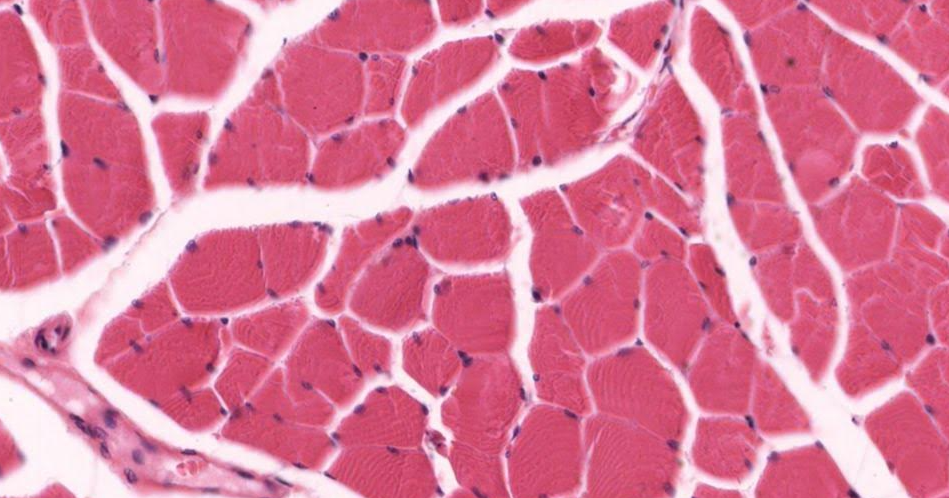

Tecido muscular esquelético transversal